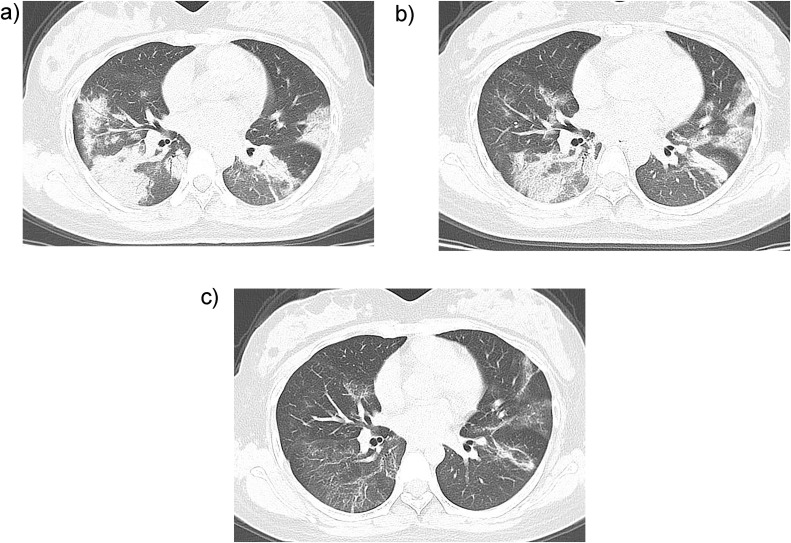

During follow-up, twelve patients (16 %) dramatically improved. A new CT showed that lesions had decreased in size by more than half in 8 cases (67 %, 8/12) after the patients had received antiviral and supportive treatment after one week of hospital admission. Among them, 3 patients showed remarkable absorption (Fig. 2 ). Four other patients showed residual interstitial abnormalities with persisting septal lines.

Fig. 2.

CT features of the disease amelioration in patient with coronavirus disease-2019. A 27-year-old female patient has fever for 10 days and pharyngalgia for 3 days, with the medical history of contacting with the infected patient. The detection of new coronavirus nucleic acid was positive. A. On admission day, CT scan shows multiple ground-glass opacities and pulmonary consolidation in both lungs. B. Three days after admission, CT scan shows that the density of the foci is lighter and the size is smaller than that at admission day. C. Seven days after treatment, re-examination of CT shows that the lesions in both lungs are further absorbed.